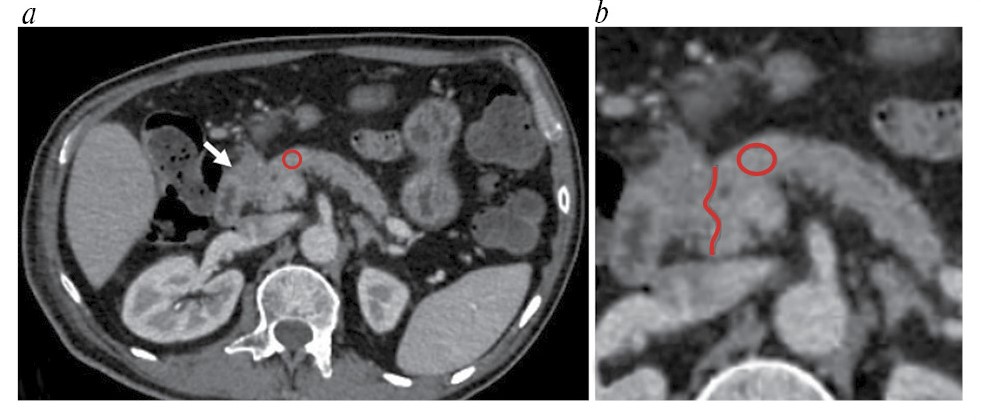

Значения рентгеновской плотности измеряли в участке ткани ПЖ площадью 0,2–0,8 см2 в области, подлежащей удалению в ходе операции. В случае новообразований при измерении отступали на расстояние 20 мм от края ново- образования для исключения из измерения зоны потенциальной десмопластической реакции (рис. 1). У пациентов с ХП измерения проводились в участке тканей, которые планировалось удалить в ходе резекционно-дренирующей операции (рис. 2). При этом участок для измерения выбирали таким образом, чтобы в него не входили кровеносные сосуды, патологические включения и образования, панкреатический проток и его боковые ветви, а также кальцинаты. В измеренных по данным МСКТ участках при патоморфологическом исследовании оценивали степень фиброза ПЖ.

Рис. 1. Пример измерения рентгеновской плотности ткани ПЖ рядом с новообразованием. МСКТ в ПФ: а – томограмма в аксиальной плоскости; b – увеличенный фрагмент томограммы. Белой стрелкой показано новообразование ПЖ, красной линией – граница новообразования, красным кругом – зона измерения.

Fig. 1. An example of measuring the X-ray density of the pancreatic tissue near a neoplasm. MSCT in the pancreatic phase (PP): a – axial plane; b – zoomed fragment of the tomogram. The white arrow shows the pancreatic neoplasm, the red line shows the boundary of the neoplasm, and the red circle indicates the measurement zone.